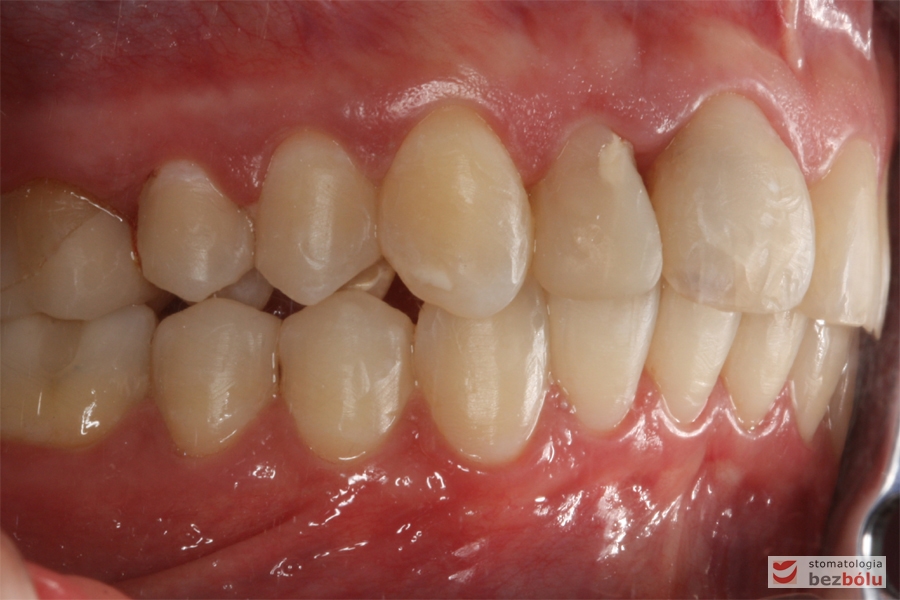

Pacjentka lat 26 zgłosiła się do gabinetu celem korekcji uśmiechu. Głównym zmartwieniem były problemy estetyczne, które znacznie wpływały na jakość życia pacjentki. Wykonano leczenie zachowawcze zębów oraz analizę cefalometryczną i analizę modeli diagnostycznych. Zaplanowano leczenie aktywne aparatem DAMON dla szczęki i żuchwy, które trwało 2 lata. Po fazie leczenia aktywnego rozpoczęto leczenie retencyjne z użyciem szyny tłoczonej dla szczęki i retainera stałego dla żuchwy.